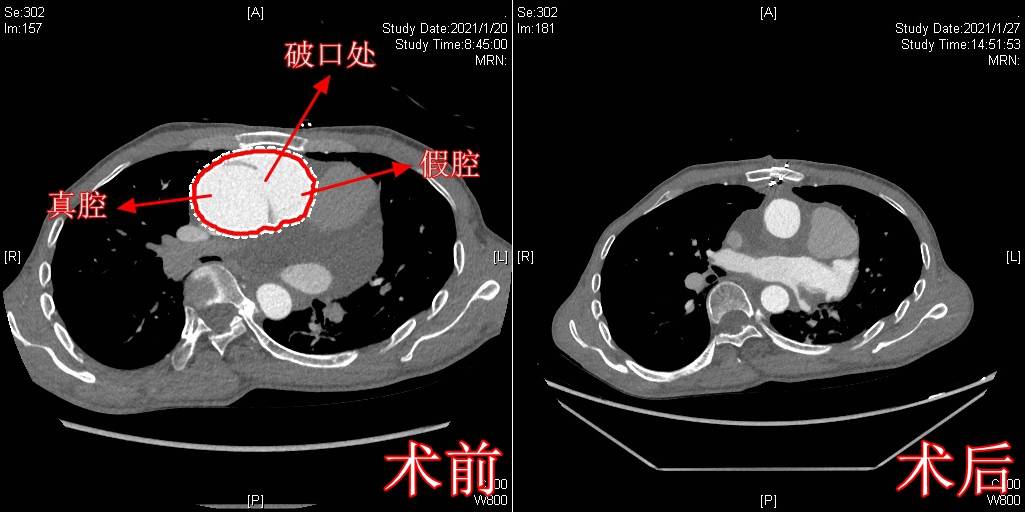

经进一步检查 , 张先生被确诊为马凡综合征合并主动脉夹层Stanford A型 。 他的主动脉夹层撕裂得非常严重 , 夹层已经波及头臂干、双侧颈总动脉及双侧锁骨下动脉 , 左颈总动脉开口重度狭窄 , 左心增大 , 同时还有心包积液 。 一系列检查结果表明 , 患者主动脉夹层已经处在破裂的边缘 , 生命危在旦夕 。

护心团队行高难度手术“拆弹”

“正常人的升主动脉直径小于35毫米 , 而张先生的却已经扩张成球形 , 直径将近是正常升主动脉的2倍 , 随时可能爆裂 , 必须尽快手术!”鉴于张先生病情危重 , 为尽快拆除这颗“不定时炸弹” , 泰心医院心外科、超声、放射、体外循环、麻醉、护理等多科室联合会诊后 , 专家们联合为患者制定了详尽的手术方案和应急预案 。